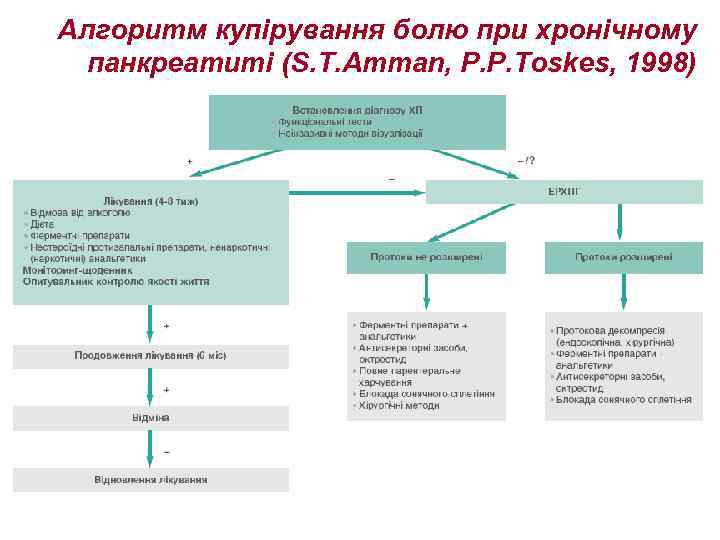

Алгоритм купірування болю при хронічному панкреатиті (S. T. Amman, P. P. Toskes, 1998)

Алгоритм купірування болю при хронічному панкреатиті (S. T. Amman, P. P. Toskes, 1998)